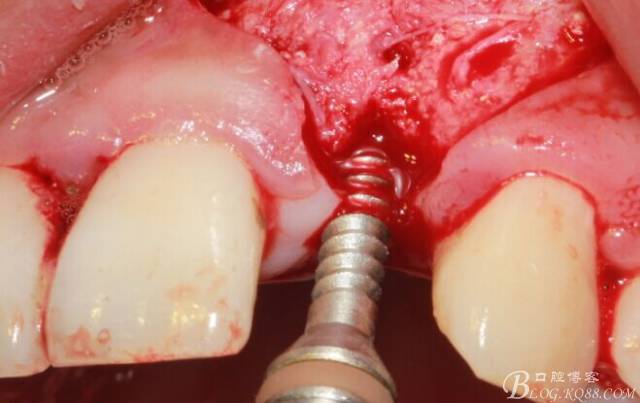

徹底搔刮拔牙窩,偏腭側(cè)備洞

順利植入植體,扭力30N。三壁骨,感覺美美的